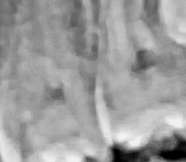

shtift-v-zube-i[...].png 237Кб, 564x600

564x600